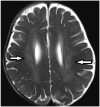

Dawson Fingers

Multiple sclerosis has a wide array of radiological findings, and many of these have their own signs. Demyelinating plaques with a perpendicular course, adjacent to the body of the lateral ventricle, present as hyperintensities on T2WI (Fig. 7) (11). They are called Dawson’s fingers and are are considered to be a relatively specific sign for MS.

fig ft0fig mode=article f1

Fig. 7

caption a4

caption a8Dawson fingers.